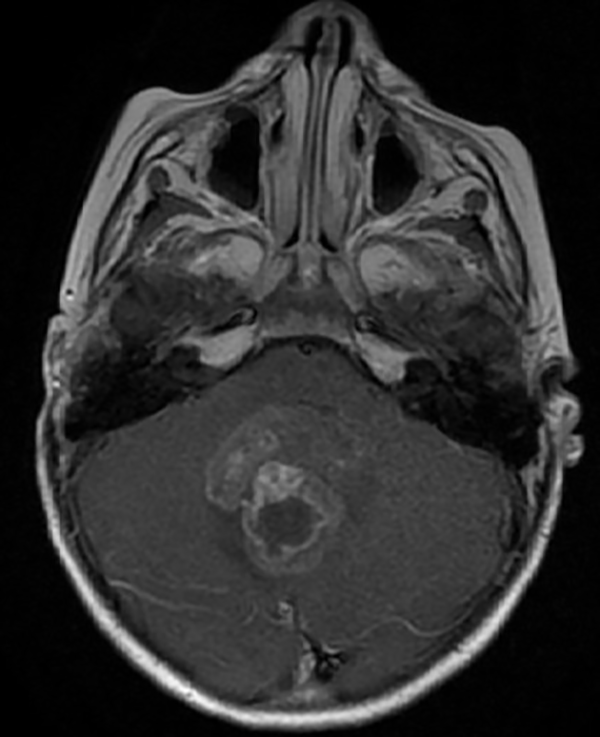

En resonancia magnética (RM) de cerebro se observa tumoración heterogénea sólida o sólido-quística con áreas de hemorragia, quistes y calcificaciones, que capta contraste en forma variable. (Fig. 1, 2, 3, 4). El patrón en espectroscopía se caracteriza por presentar pico de Colina (Cho) y descenso de N-Acetilaspartato (NAA).

Fig 1:

RM corte axial, secuencia T1 con contraste. Se observa neoformación medial, solido-quística, heterogénea de bordes irregulares en la topografía del VI ventrículo que ocupa la totalidad del mismo, que realza en forma heterogénea tras la administración del contraste.